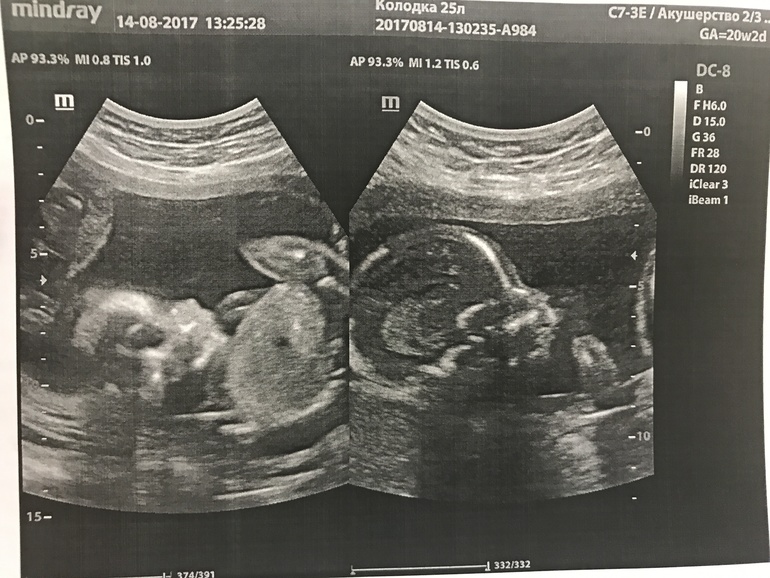

Тайна раскрыта или поход на 2 скрининг узи :)

УЗИ, КТГ, доплер, скрининг, ХГЧ и другие анализыВсем привет! Девочки, пришли только с УЗИ. У нас все хорошо, все по срокам.... ииииииии у нас королевская двойня!

Слева девочка, справа мальчик)